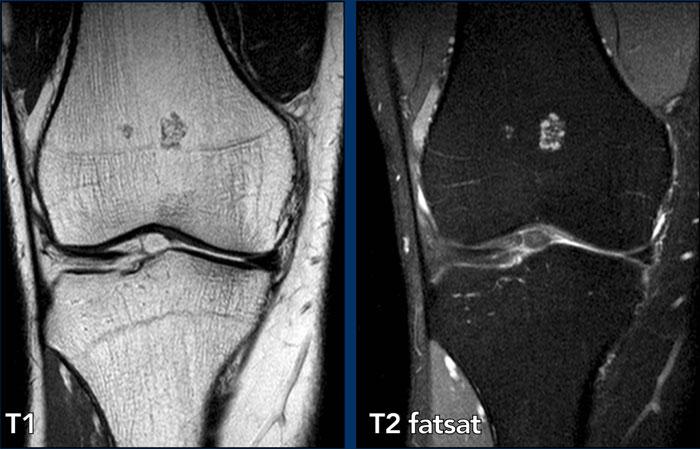

Hình ảnh

X-quang: Có vùng vôi hóa dạng sụn ở thân xương đùi xa mà không có hiện tượng xói mòn vỏ xương.

MRI: Hình ảnh T1W mặt phẳng đứng dọc cho thấy khối u sụn đa nốt không tiếp xúc với vỏ xương phía trước hoặc phía sau. Tổn thương có kích thước 38 mm.

Hình ảnh T1 mặt cắt ngang không cho thấy hiện tượng xói mòn vỏ xương.

Kết luận

Enchondroma.

Lưu ý

Đối với các tổn thương < 5 cm, miễn là tổn thương sụn không lan đến vỏ xương,

và không có phù tủy xương xung quanh hoặc viêm màng xương, chúng tôi xem đó

là u sụn nội xương. Không cần theo dõi thêm.